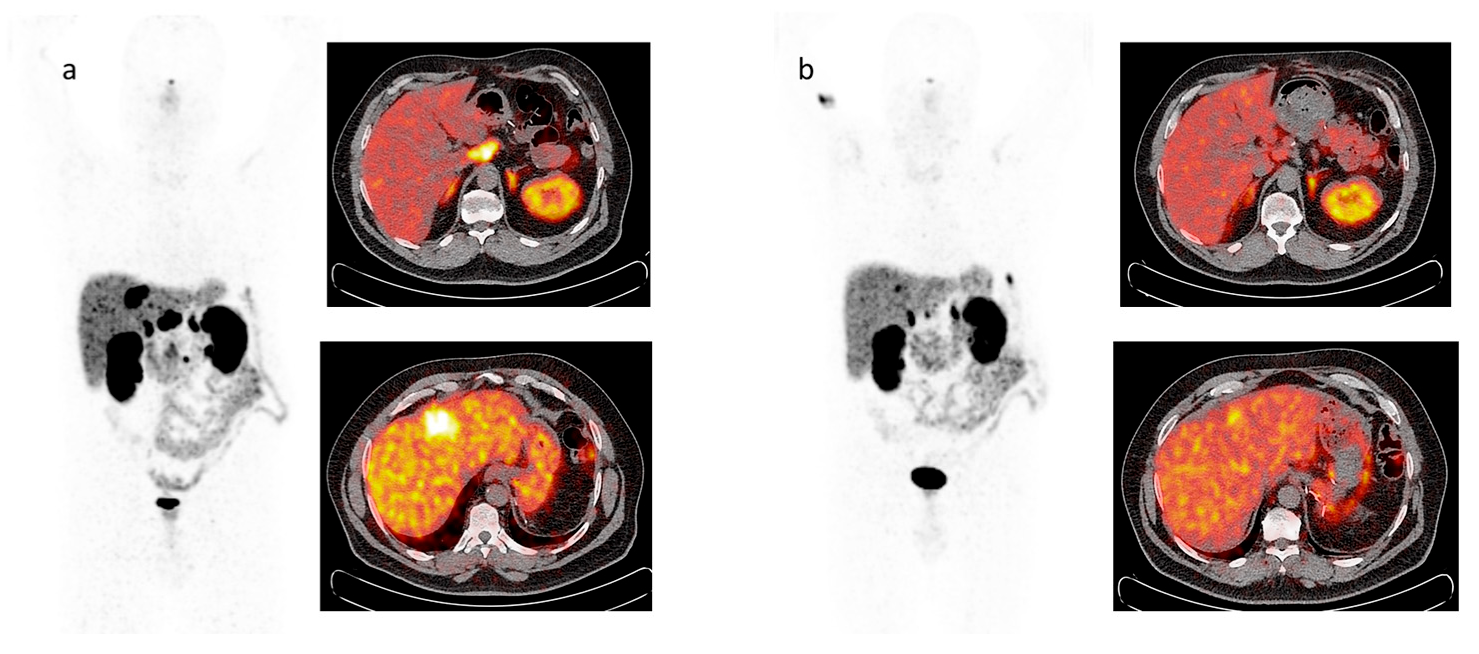

5. Imaging Analysis

6. Functional Imaging by 18F-FDG PET/CT

8. Response to Therapy: Which Criteria?